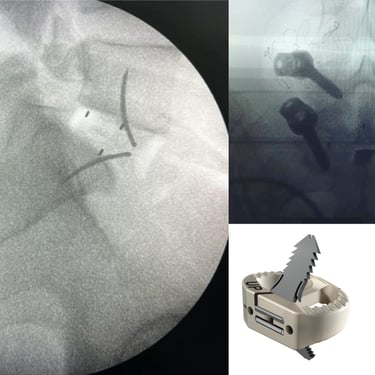

La cirugía ALIF (Anterior Lumbar Interbody Fusion), o Fusión Lumbar Intercorporal Anterior, es una técnica quirúrgica utilizada para tratar patologías de la columna lumbar como la degeneración discal, la inestabilidad vertebral o las hernias lumbares recurrentes. Mediante un abordaje anterior, se extrae el disco dañado y se coloca un injerto o caja intersomática que permite lograr la fusión estable entre las vértebras. Este procedimiento favorece una mejor restauración del espacio discal, alineación lumbar y preservación muscular. La cirugía ALIF es realizada por un equipo especializado en neurocirugía de columna, garantizando precisión y resultados funcionales óptimos.